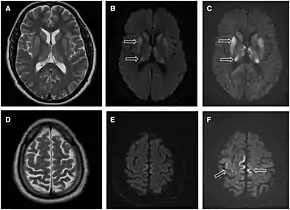

| Magnetic resonance image of sporadic CJD[2] | |

Imaging of the brain may be performed during medical evaluation, both to rule out other causes and to obtain supportive evidence for diagnosis. Imaging findings are variable in their appearance, and also variable in sensitivity and specificity.[43] While imaging plays a lesser role in diagnosis of CJD,[44] characteristic findings on brain MRI in some cases may precede onset of clinical manifestations.[45]

Brain MRI is the most useful imaging modality for changes related to CJD. Of the MRI sequences, diffuse-weighted imaging sequences are most sensitive.[46] Characteristic findings are as follows:

- Focal or diffuse diffusion-restriction involving the cerebral cortex and/or basal ganglia. In about 24% of cases DWI shows only cortical hyperintensity; in 68%, cortical and subcortical abnormalities; and in 5%, only subcortical anomalies.[47] The most iconic and striking cortical abnormality has been called "cortical ribboning" or "cortical ribbon sign" due to hyperintensities resembling ribbons appearing in the cortex on MRI.[48] The involvement of the thalamus can be found in sCJD, is even stronger and constant in vCJD.[49]

- Varying degree of symmetric T2 hyperintense signal changes in the basal ganglia (i.e., caudate and putamen), and to a lesser extent globus pallidus and occipital cortex.[44]